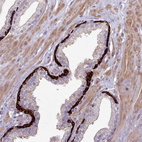

Immunohistochemical staining of human skin shows strong membranous positivity in squamous epithelial cells.